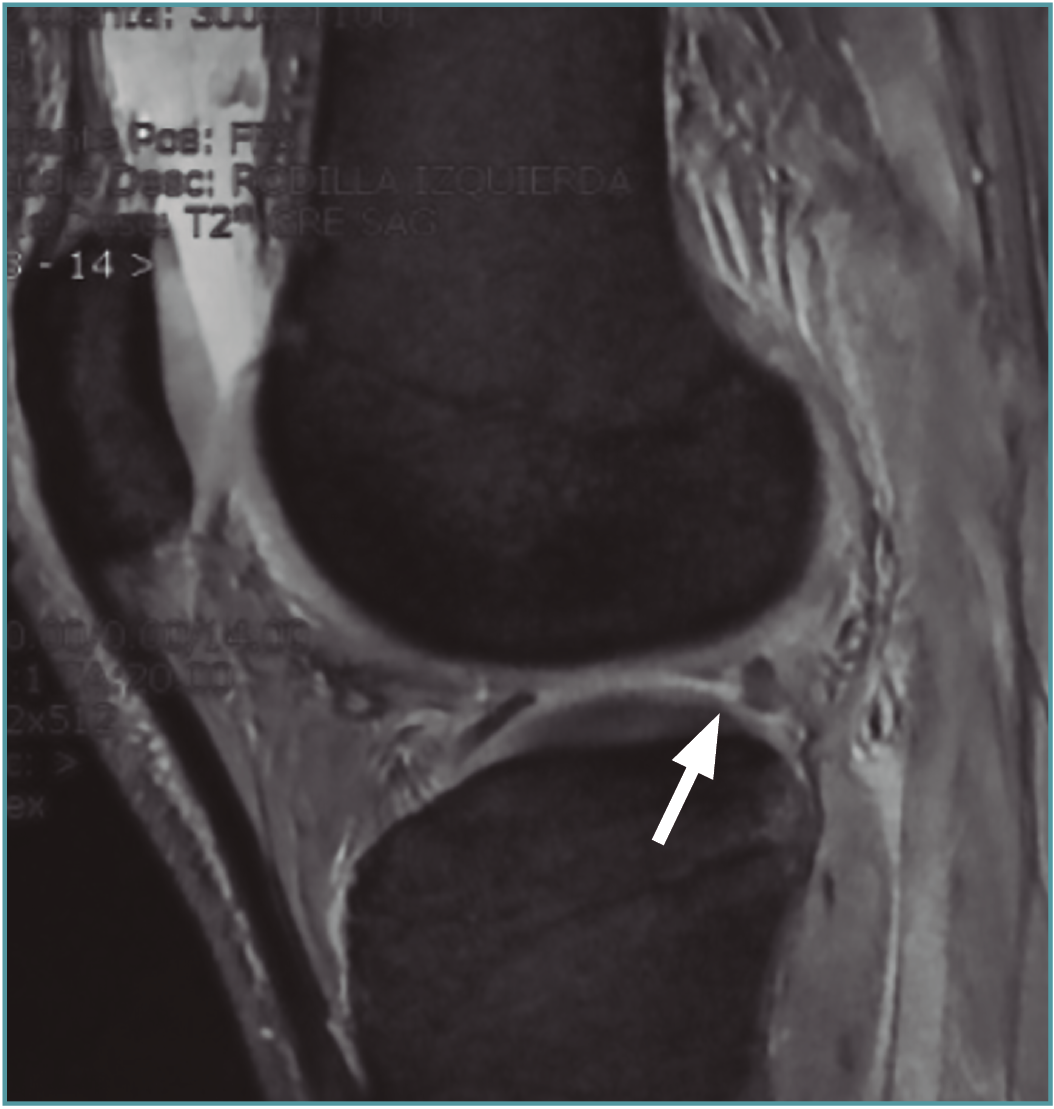

Se han descrito varios signos radiológicos relacionados con las roturas de la raíz y las roturas radiales en general, como son el signo del triángulo truncado, el signo de la hendidura en el plano coronal y el clásico signo del menisco fantasma en el plano sagital(57). El signo del menisco fantasma o del menisco vacío se observa en el contexto de una extensa rotura radial que atraviesa el espesor completo meniscal, o posterior a meniscectomía, cuando el plano de corte se realiza en el plano exacto de la rotura(58)(Figura 6).

Figura 6. Imagen sagital de resonancia magnética en la que puede apreciarse el signo del “menisco fantasma” (flecha).